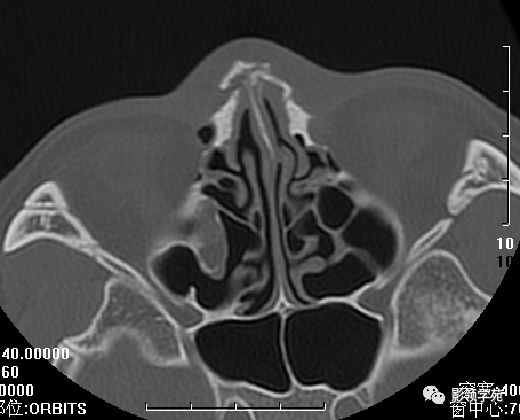

HRCT

- 横断面:听眶下线

鼻骨横断面HRCT